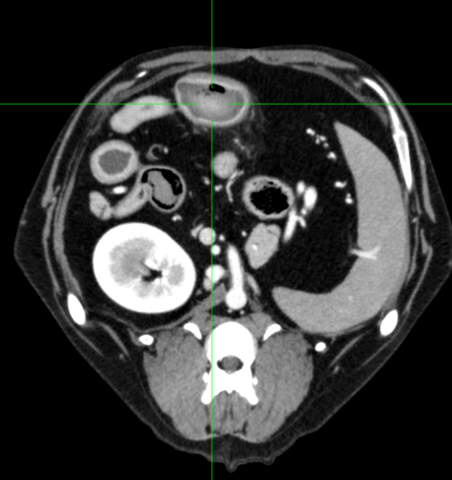

精査のため、CT検査を実施。

空腸近位部に35 mm程の構造物を確認。

それより近位で拡張、液体貯留、粘膜の不整を確認。

それより遠位では異常なし。

また右肺中葉全域と左肺前葉腹側の一部が無気肺になっていた。

以上の結果から、異物誤飲による腸閉塞、またそれによる嘔吐・吐出により、誤嚥性肺炎を引き起こしていると診断した。